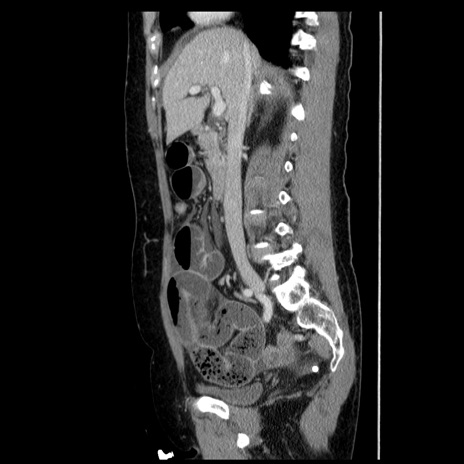

症例6(矢状断像)

【症例】50歳代女性

【主訴】下腹部痛

【現病歴】本日朝より下痢2回あり。 昼食を食べた後、嘔吐3回、下腹部痛認め、症状軽快せず、当院救急搬送。

最終食事:本日昼(生ものなし)。 昨日の夜、刺身を食ぺたとのこと。周囲に同様の症状の者なし。普段、排便は毎日あるとのこと。

【既往歴】卵巣癌術後(8年前に当院で卵巣摘出)

【身体所見】 意識清明、腹部:平坦、腸蠕動音→、やや硬、下腹部自発痛・圧痛あり、反跳痛あり、筋性防御なし。

【データ】WBC 16000、CRP 0.01